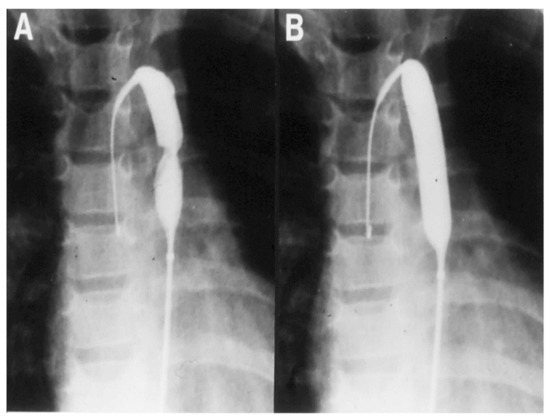

4. Coarctation of the Aorta

4.3. Type of Intervention